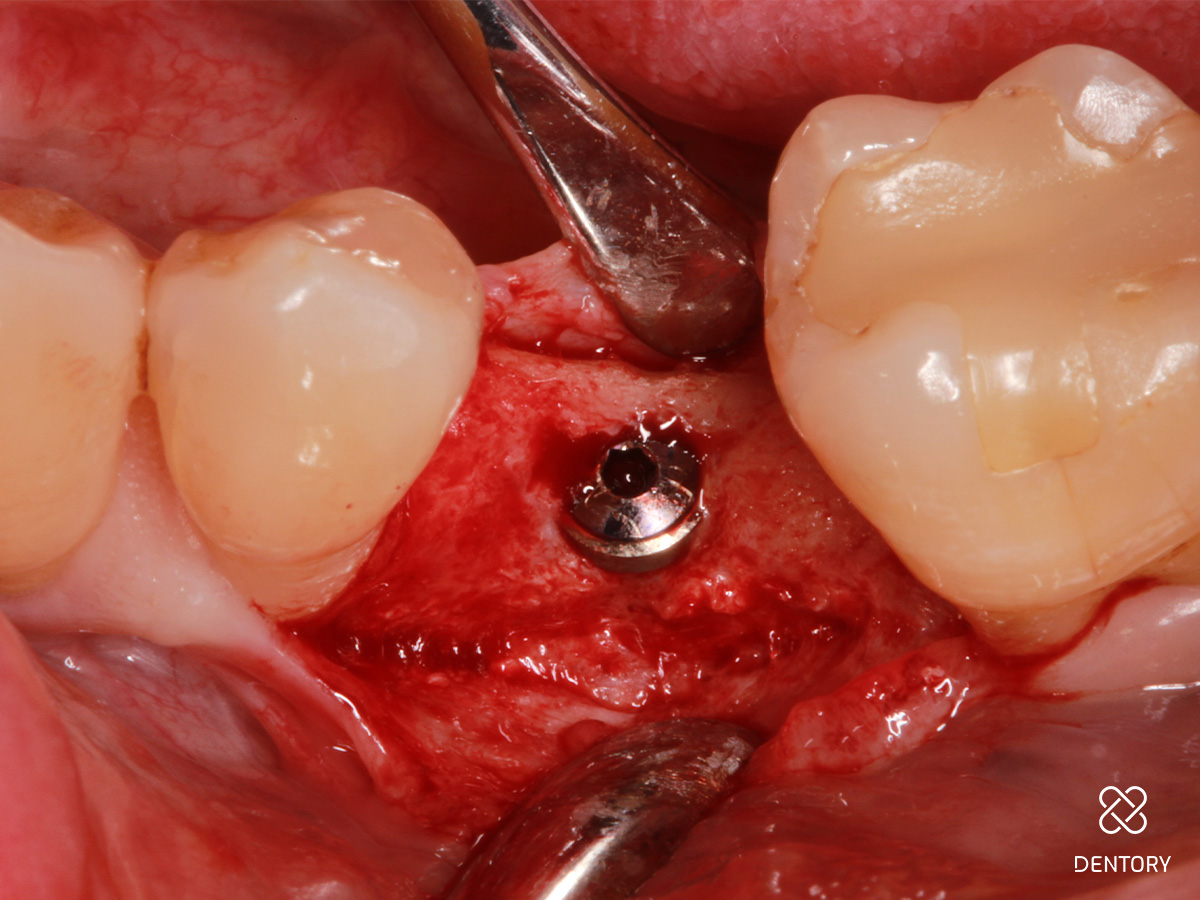

Abbildung 4

In der Lateralansicht zeigt sich ein moderater Dehiszenzdefekt bei gut erhaltener Knochenstruktur an den Nachbarzähnen, welche die Knochenregeneration unterstützen werden.